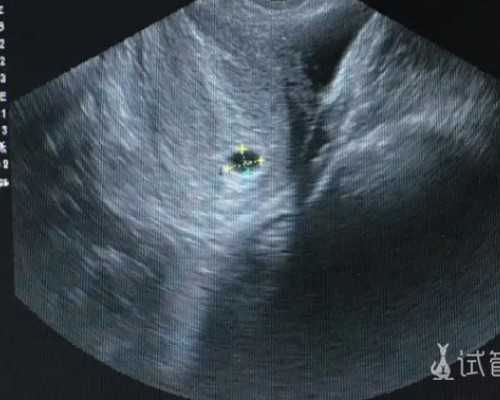

3.如无做B超,请在怀孕7周做B超

5.B超证明怀孕足6周或以上,胚芽达3MM或以上就可鉴定